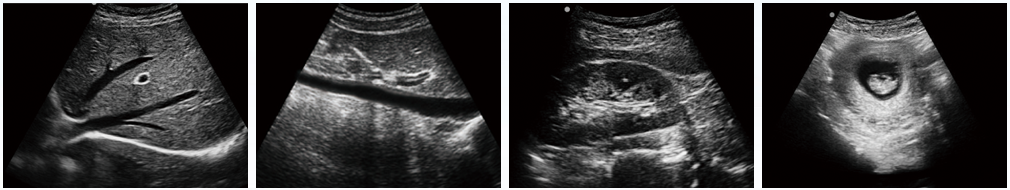

DW-360便攜式B超機臨床圖像

設備用途說明:主要應用于腹部、淺表組織、生殖系統、泌尿系統等器官的檢查